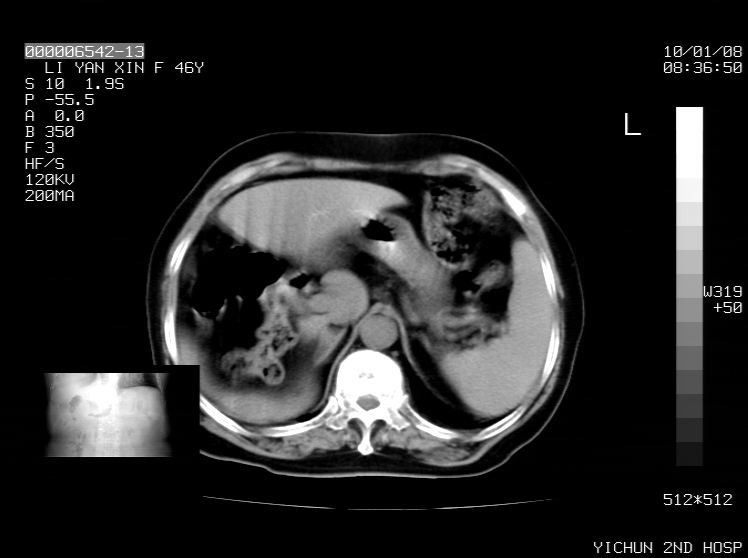

标题: CT24039:请会诊,女70岁,彩超考虑胆囊结石 [打印本页]

标题: CT24039:请会诊,女70岁,彩超考虑胆囊结石

右侧膈膨升,胆囊壁厚,右侧肾脏缺如。病史?

右侧膈膨升,右肾脏切除术后

右侧膈膨升,肝内钙化灶,胆囊壁厚,右侧肾脏缺如。病史?

右膈膨出,肝脏变异,肝内钙化,右肾缺如,脾大。

右侧膈膨升,肝内胆管结石?

右侧肾脏缺如。病史?

右侧膈膨升,胆囊壁厚,右侧肾脏缺如,增强,腔静脉旁是否是移位肾

肝脏变异致膈升高,肝左叶肝内胆管结石.右肾萎缩,左肾代偿肥大.

胆囊ct未见确切异常,请结合b超。右侧肾窝未见确切肾脏影,右肾萎缩?异位?

右侧膈膨升,肝内钙化灶,胆囊壁厚,右肾萎缩或发育不良。